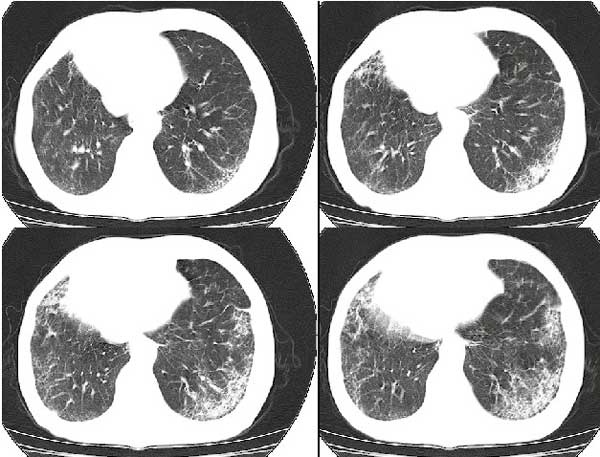

以下是引用扬仪在2005-5-12 20:46:40的发言:[br]右肺呈术后改变;双侧肺野散在分布斑片状、点状高密度病灶,(似可见“树芽征”);左上尖后段见斑团状高密度病灶(2个层面?),边缘毛糙,段性分布,与斜裂相邻,临近胸膜粘连;增强示病灶边缘强化,内呈水样密度;心影、纵隔右移,内可见4r淋巴结肿大。[br]意见:1、双肺继发性肺结核,左上为干酪病灶;[br] 2、矽肺合并感染;[br] 3、建议抗痨+抗炎。 [br]愚人之见,请高人指教!